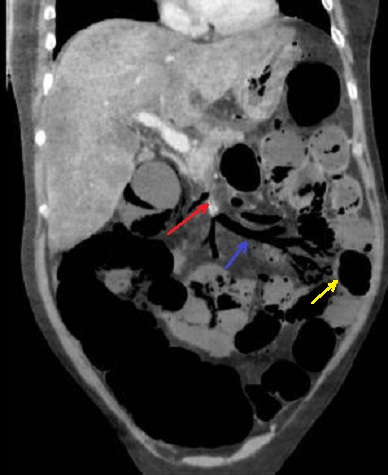

Ischemie

mesenterique de l'intestin par thrombose veineuse en

coupe TDM coronale phase veineuse : Image de

thrombus d'une branche de la veine mesenterique

superieure ( fleche rouge ) et aspect de

aereobie-mesenterique de veine mesenterique se

voyait si net ( fleche violet ) et image de

defaut de rehaussement

de la paroi de l'intestin ( fleche jaune ) . |